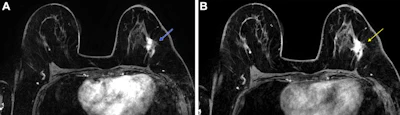

Post-neoadjuvant chemotherapy (NAC) MRI scans in a 66-year-old woman with invasive breast cancer show a lesion that appears fragmented in the first postcontrast axial T1-weighted image (arrow in A) but becomes more conspicuous and homogeneous in the last delayed phase (arrow in B). Despite these visual differences, response classification was identical between abbreviated and full diagnostic MRI. Pathologic analysis confirmed a partial response with residual invasive carcinoma.RSNA